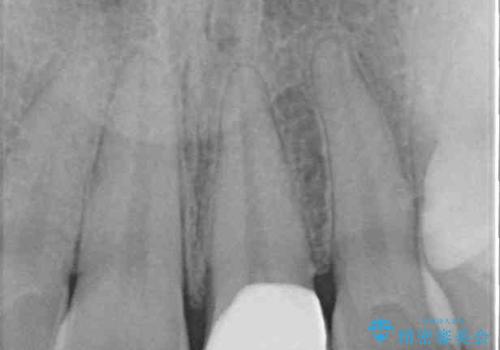

- ぶつけて欠けてしまった前歯を樹脂でつめていたものの、すり減りや変色が顕著とのことで来院された患者様です。

詰め物の詰め直しとオールセラミッククラウンの双方をご提案し、患者様ご希望によりオールセラミッククラウンにて補綴治療を行うこととしました。

歯列全体に表面の着色があったため、クリーニングとホワイトニングを事前に行い、ホワイトニング後1ヶ月ほどおいて、色の落ち着いたところで色合わせを行いました。

本物の歯のような仕上がりとなりました。